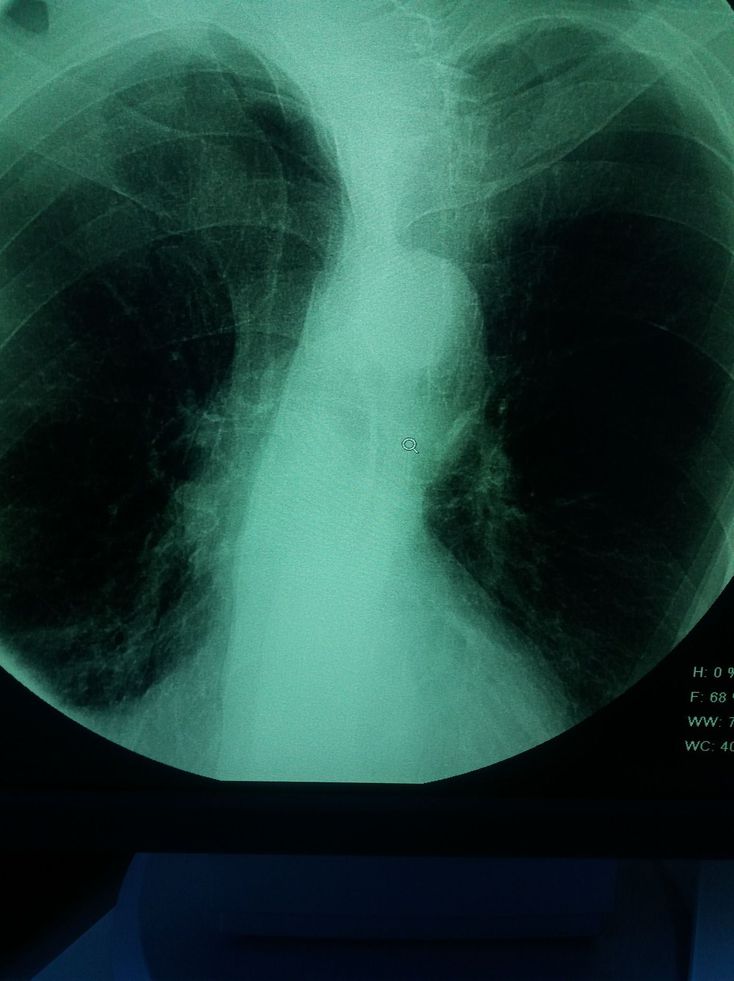

What do you see

Some sort of x-thorax, the rest is a mystery to be honest.

Tuberculos right lung apex!